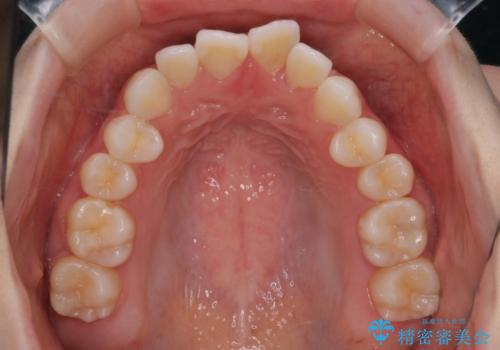

【審美装置】前歯で噛めない!抜歯しないで治したい

- 前歯の捻転とかみ合わせを主訴に来院されました。今回は抜歯をせずにIPRを実施し、並べる計画を立てました。

ワイヤー矯正を行いながら、顎間ゴムを患者さまにご協力していただき、短い期間で終了できました。